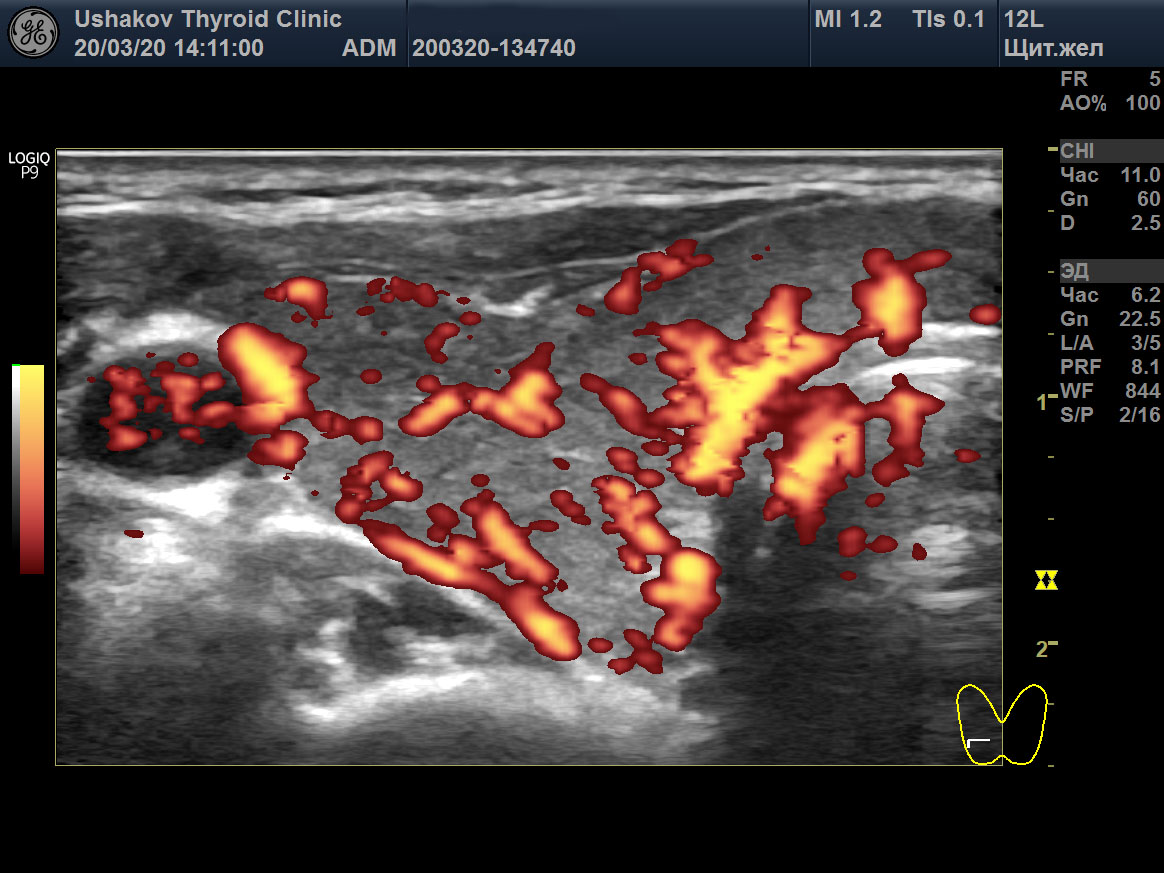

Пример такого случая представлен на

снимках ниже, где показаны две доли ЩЖ пациентки 31 года в режиме ЭДК и ПССК в системе верхних щитовидных артерий (ВЩА). Интенсивность кровотока при ЭДК усилена до значительной степени, а ПССК – до умеренно избыточной величины (норма 20-30 см/с [127]).

Рисунок 1 Левая и правая доли ЩЖ пациентки 31 года (поперечные и продольные проекции в режиме ЭДК; ПССК в режиме ЦДК), УЗИ 20.03.2020. Объём ЩЖ 9,1 мл (рост 170 см, масса 50 кг). Данные анализа крови от 18.03.2020: ТТГ 33,6 мЕд/л [0,4-4,0], Т4св. 6,7 пмоль/л [9,0-19,0], Т3св. 4,1 пмоль/л [3,0-5,6], АТТПО >1000 Ед/мл [<5,6], АТ-ТГ 368,8 Ед/мл [<18]. ПССК в системе ВЩА слева и справа 54 см/с. Концентрация йода в моче 200 мкг/л. Медикаменты не принимает продолжительный период.

Рисунок 1 продолжение

Рисунок 1 окончание |

В результате при обращении в нашу Клинику были выявлены признаки значительного перенапряжения ЩЖ по данным УЗИ в виде значительной интенсификации тиреоидного кровотока (

рис. 1). Эта избыточная стимуляция ЩЖ со стороны гипофиза (ТТГ 33,6 мЕд/) и периферической ВНС, тем не менее, сопровождалась